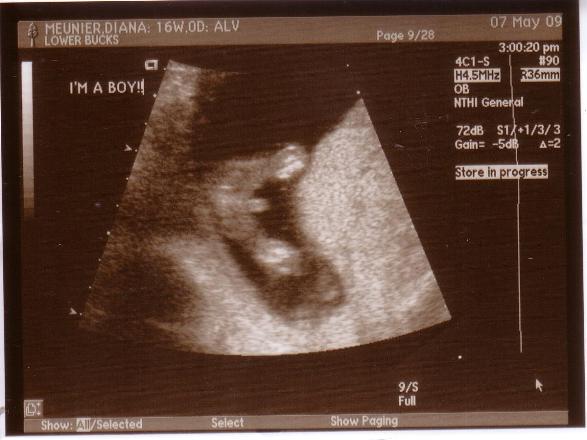

Re: Girls that had a 16 week sono......

i went at 16 weeks as a follow up to 12 weeks b/c they saw a cyst on my ovary. i guess it was rather large so they wanted to keep an eye on it.

so i go in at 16 weeks and the tech asked if we wanted to know b/c she may be able to tell. and sure enough, little guy started flashing us. she cracked up and was like..well..thats a boy!

here's our pic..LOL

If its a boy, they can be more accurate. if they dont see a wee wee yet, they will probably make you wait until 20 weeks just to be sure.

Image Attachment(s):